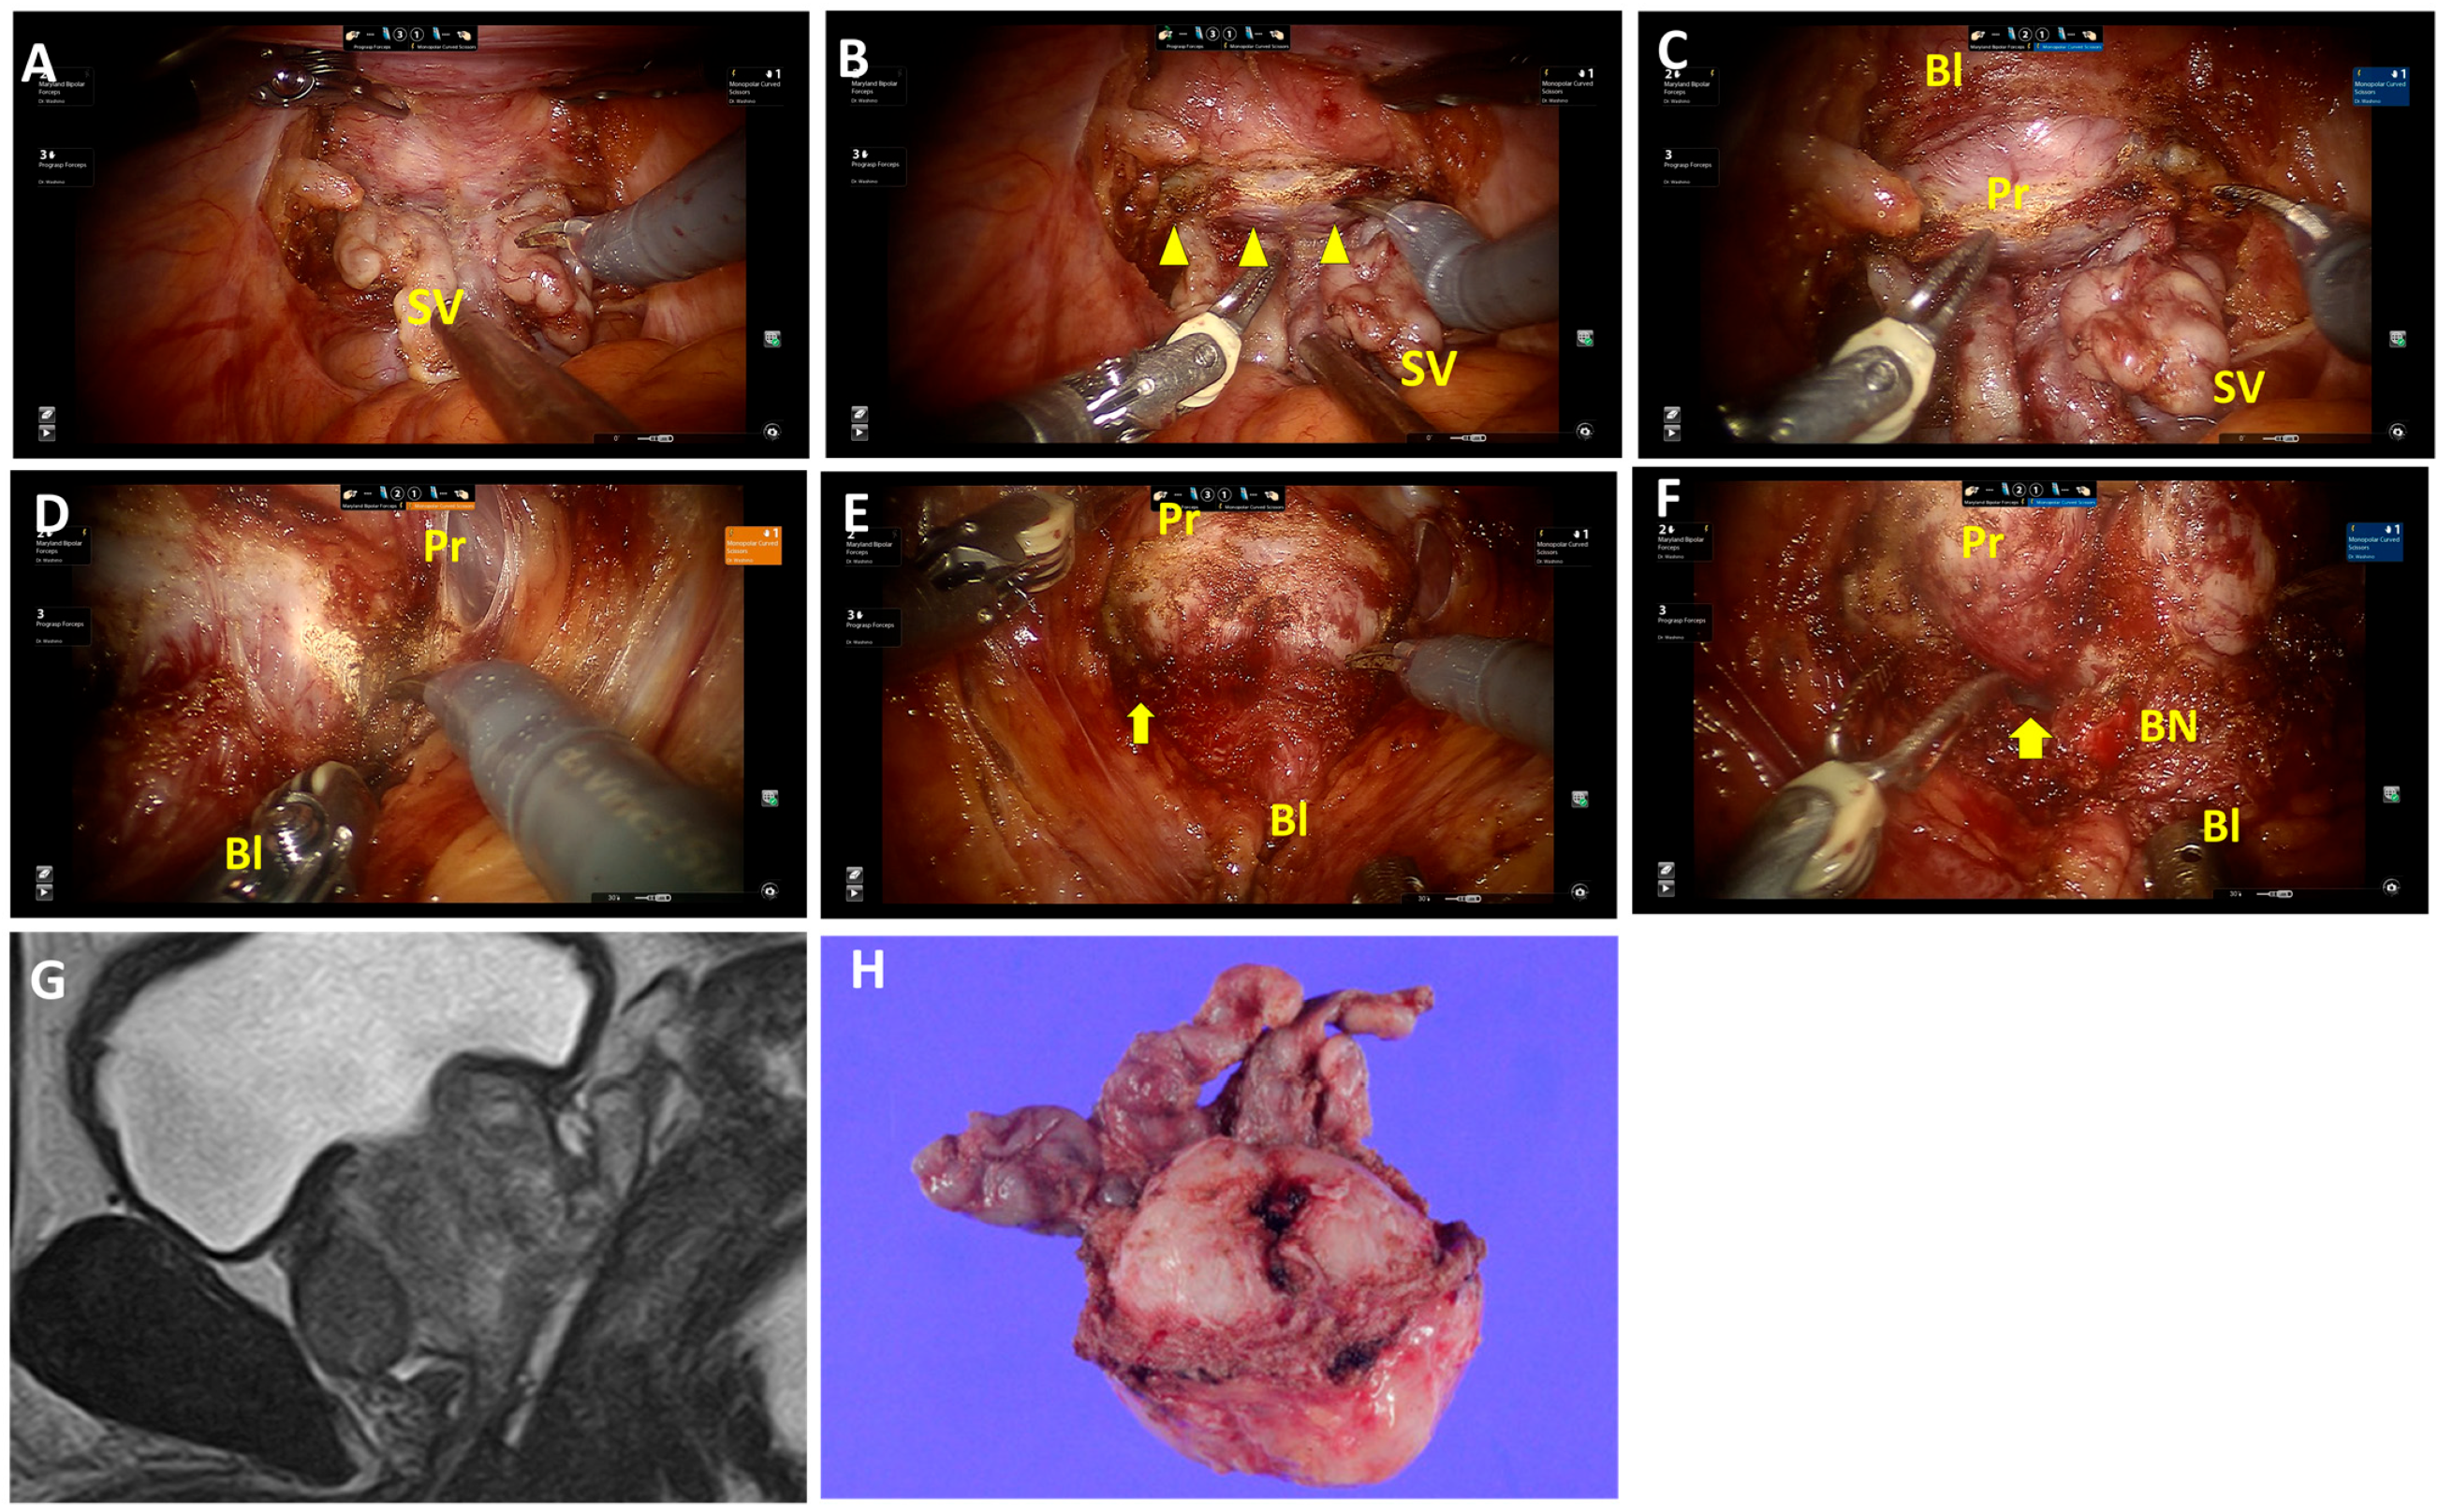

Fat tissues and vessels overlap the retrotrigonal layer (Figure 1A; Video S1) and are abundant on the lateral sides. Fat tissues and vessels, followed by the retrotrigonal layer, are transected approximately 0.5–1.0 cm above the seminal vesicle and deferens vasa. This allows the bladder wall to be separated anteriorly from the prostate (Figure 1B,C). In cases with an enlarged prostate or prominent median lobes, the retrotrigonal layer tends to be thinner, and the surface of the prostatic pseudocapsule can easily be identified after transection (Figure 2A,B; Video S2). Then, this layer can be developed anteriorly (Figure 2C). For nerve-sparing procedures, the lateral transection of the retrotrigonal layer and/or overlapping fat tissues and vessels are preserved.

The detrusor apron at the bladder neck is dissected and developed laterally (Figure 1D and Figure 2D). Then, the posterior space is opened laterally prior to the bladder neck opening (Figure 1D). Carefully, detrusor muscles are detached from the prostate, revealing the longitudinal urethral muscles in the center (Figure 1E). Then, the anterior urethral muscles are dissected to open the bladder neck, followed by the posterior bladder neck. The bladder neck is preserved (Figure 1F and Figure 2F). This procedure was consistently applied, except in cases where the prostate tumor was located near the proximal edge, adjacent to the bladder neck.

4.2. Cases with Large Prostate Glands and Median Lobes

Figure 2. Surgical techniques of the retrotrigonal layer dissection from the posterior approach and bladder neck preservation in patients with an enlarged prostate. (A) Isolation of the seminal vesicle and dissection of deferens vasa in a posterior approach. (B) The retrotrigonal layer, pinkish longitudinal tissue, is transected (triangles). (C) The surface of the prostatic pseudocapsule can easily be identified after transection. This layer can be developed anteriorly. (D) Right lateral approach in bladder neck dissection. (E) Detrusor muscles are detached from the prostate. The posterior space is visible laterally (arrows). (F) The bladder neck is preserved (arrows). (G,H) MRI sagittal view and macroscopic findings of the prostate and seminal vesicle. Enlargement of the prostate gland is visible and the surface of the prostatic pseudocapsule at the protrusion site is exposed (H). SV, seminal vesicles; Bl, bladder; Pr, prostate; BN, bladder neck.